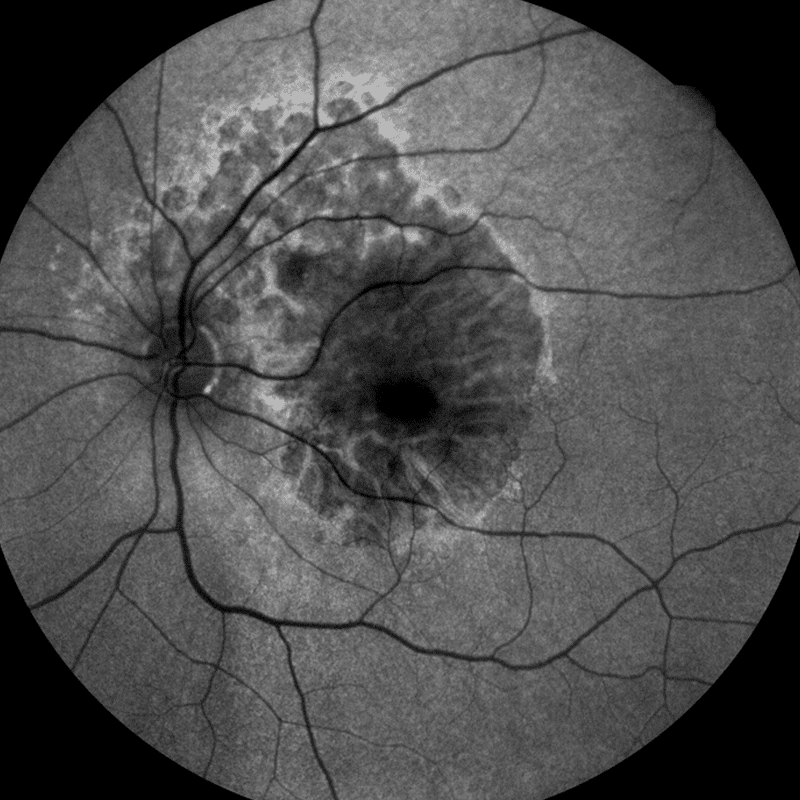

- Autofluorescence allows a look at the RPE (Retinal Pigment Epithelium) layer integrity

The confocal nature of this device enables highly detailed and sharp contrast autofluorescence images. This is achieved in one shot and does not use image averaging. In addition, it is able to scan through cataract and other media opacities.